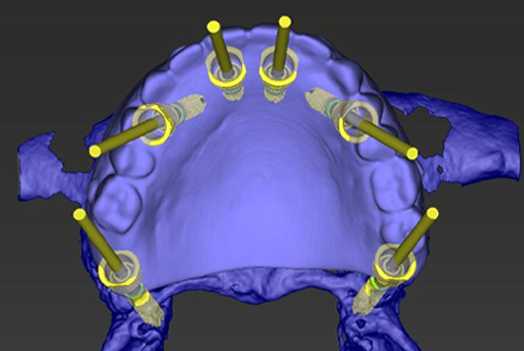

- Acesso à Odontologia Digital: Scanner intra-oral | Cirurgias Guiadas | Planejamento Reab. Computadorizado.

Planejamento Digital

Guia Cirurgico

Instalação Implantes

- Planejamento reverso e Guias Cirúrgicos